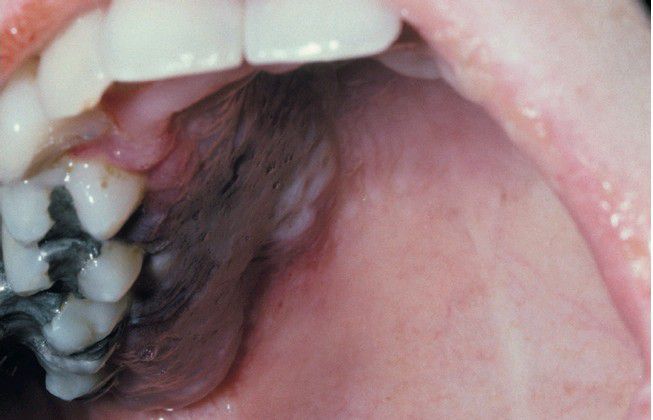

. This young woman developed a painful purplish swelling of her hard palate after induction chemotherapy for leukemia.